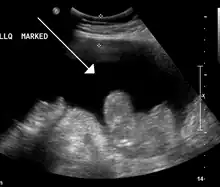

- Échographie abdominale : très sensible pour détecter les épanchements liquidiens, elle permet d'observer une lame d'ascite, notamment au niveau des flancs, de l'espace interhépatorénal (de Morison) et du cul-de-sac de Douglas.